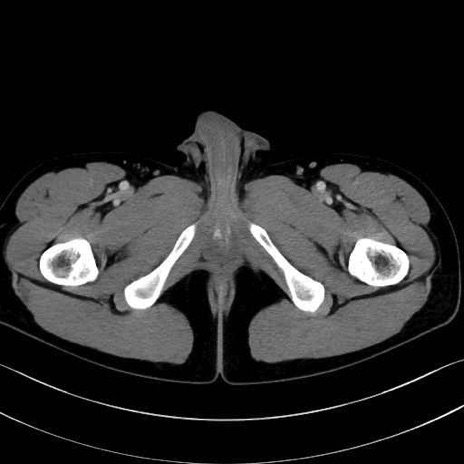

精嚢(seminal vesicle)のCT画像における解剖

症例

【症例】20歳代 男性 スクリーニング